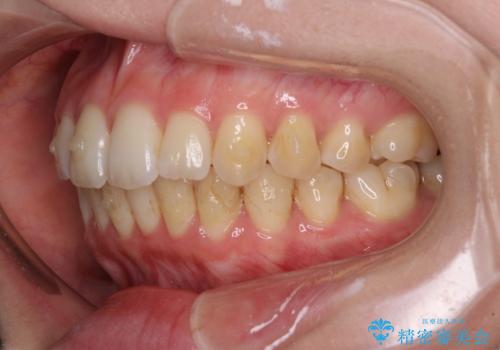

- 上下前歯のデコボコと深い咬み合わせを気にして来院された患者様です。

インビザラインによる上下歯列の拡大と、IPR(歯と歯の間を削る)にるスペースの獲得により、前歯のデコボコを改善することとしました。

上の前歯をもう少し整えたかったのですが、患者様の治療を早く終了させたいという希望により、細かい叢生を残しての終了となりました。